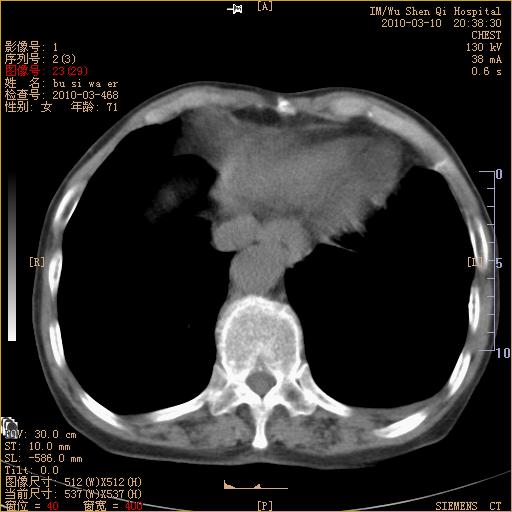

以下是引用随光逐影在2010-3-11 0:41:00的发言:[br]1)考虑左肺及右肺上叶继发性肺结核并左肺炎症感染。2)左侧支气管内膜结核可能;建议必要时行纤支镜检查。3)肺气肿。4)心包膜增厚(或少量心包积液)。5)左侧胸腔积液。